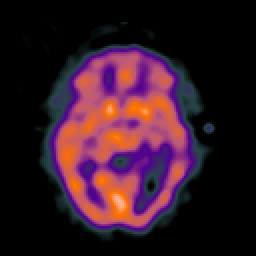

SPECT TC Study #5 -- Slice #26

[Home][Help][Clinical][Tour 1][Tour 2][Tour 3] Slice 26